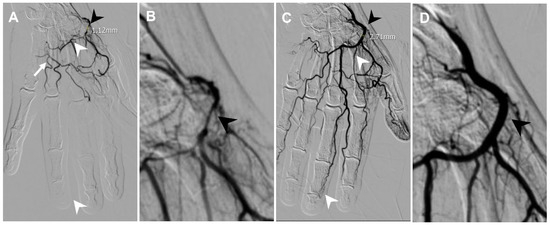

3.1. Lateral Epicondylitis

3.3. Triangular Fibrocartilage Complex (TFCC) Tear

3.5. nd-4th Metatarsalgia

| Post-traumatic foot pain | Arcuate artery | 1.75 | 2.46 |

| Finger OA | Radial artery | 1.12 | 2.71 |

| Secondary stiff shoulder | Thoracoacromial artery | 1.12 | 1.96 |